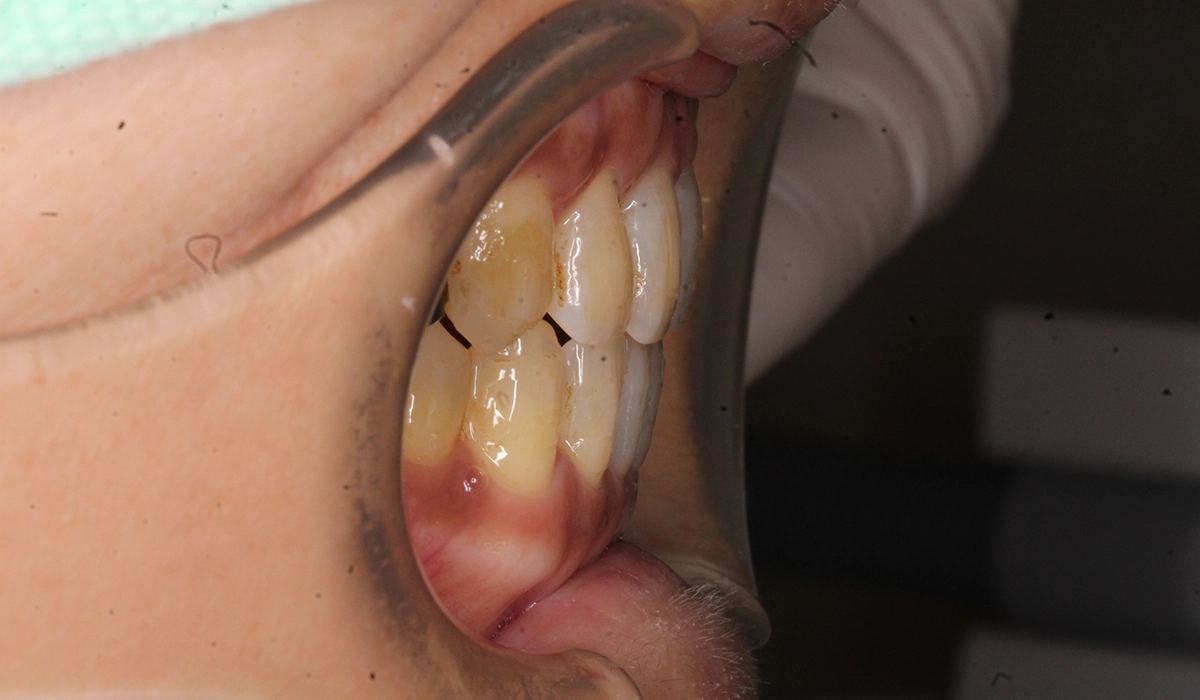

術前:左側